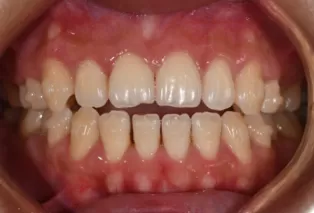

Photos intra-orales après traitement